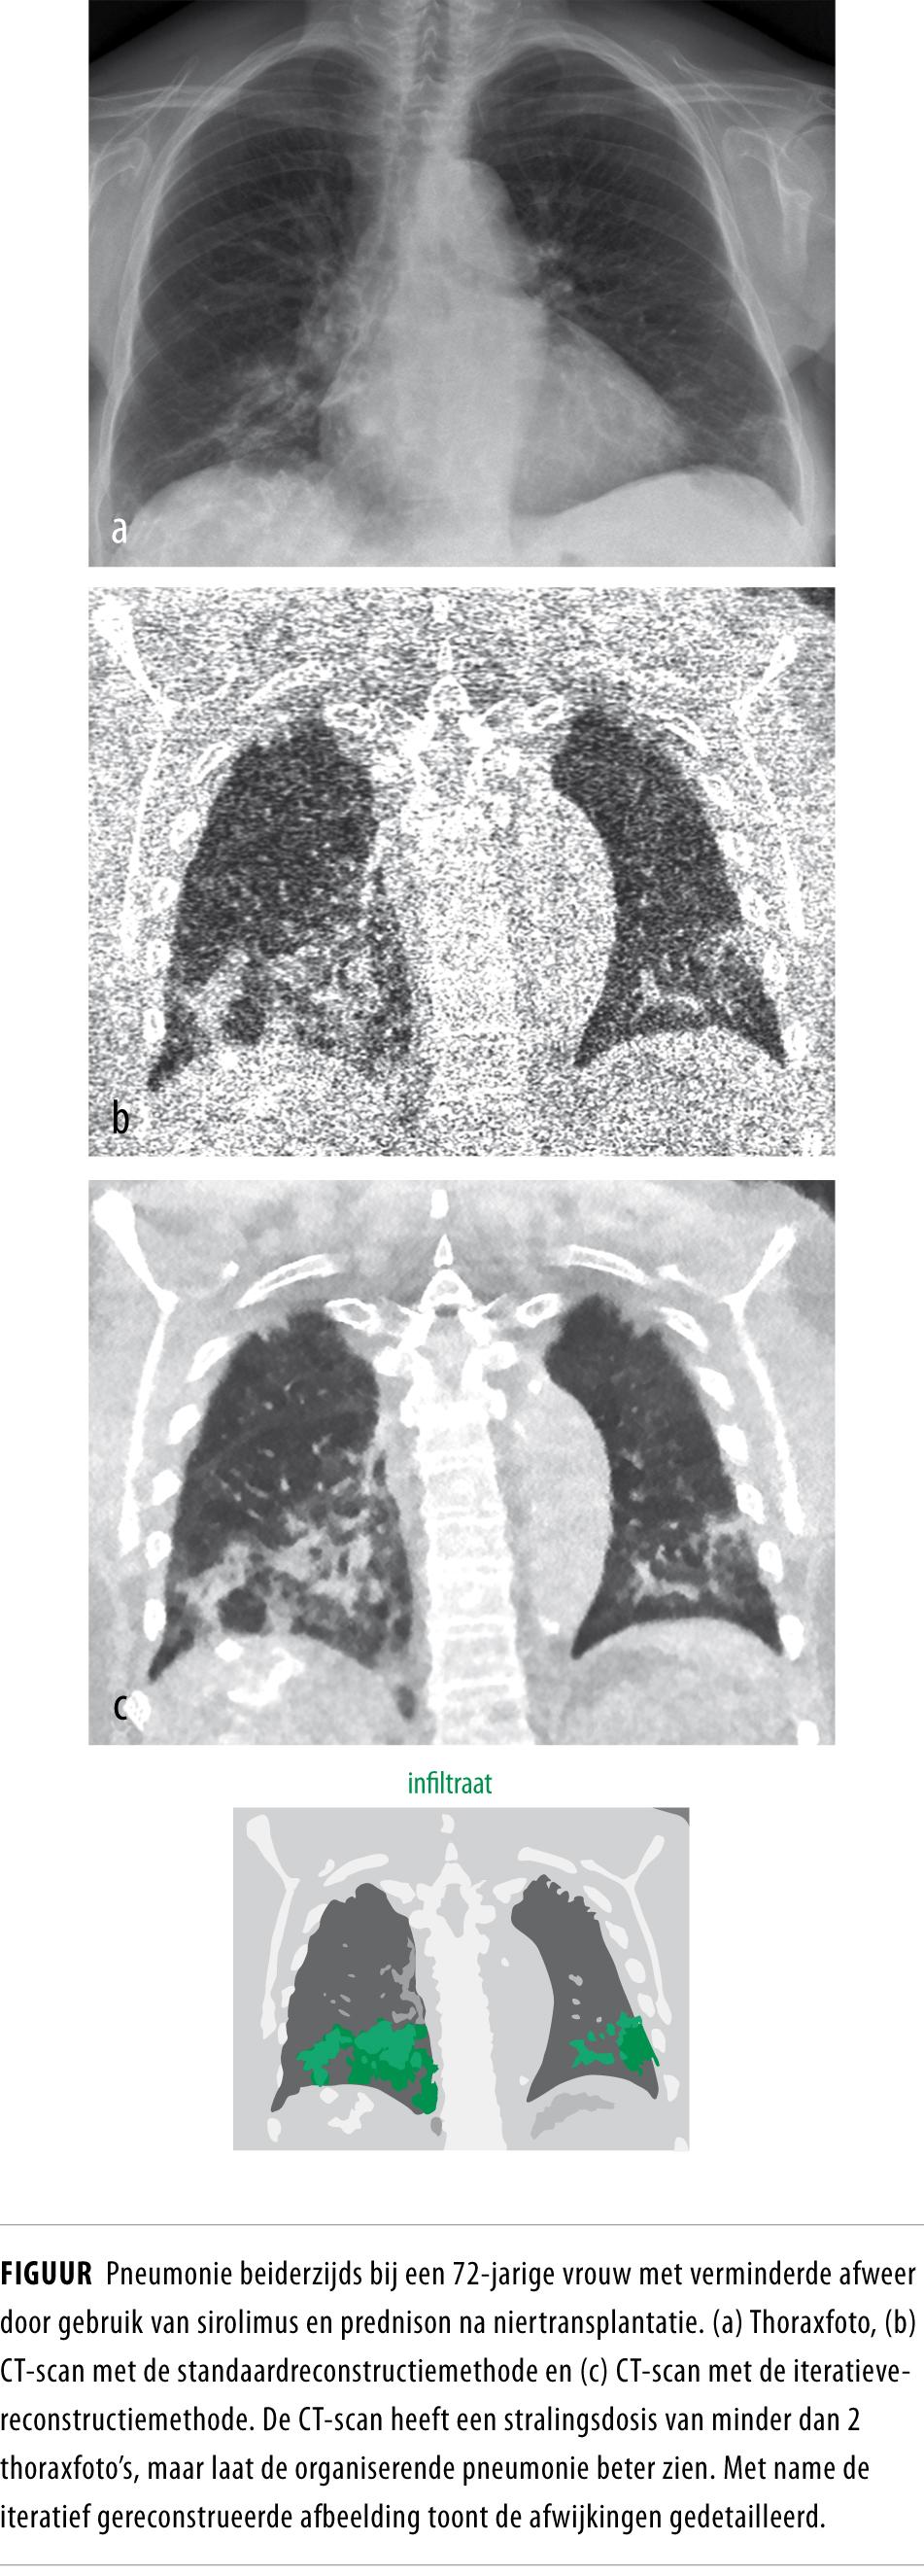

Het aantal CT-scans is gedurende de afgelopen jaren toegenomen. Om de individuele stralingsdosis te verlagen zijn nieuwe CT-technieken ontwikkeld. Met deze technieken kunnen scans gemaakt worden die de stralingsdosis van conventionele röntgenfoto’s benaderen. De röntgenstralingsdosis vormt in de toekomst dus mogelijk geen beperking meer voor het maken van CT-scans. De indicatie voor CT-scans zal hierdoor verruimen en lagedosis-CT-scans zullen in toenemende mate de conventionele röntgenfoto gaan vervangen.